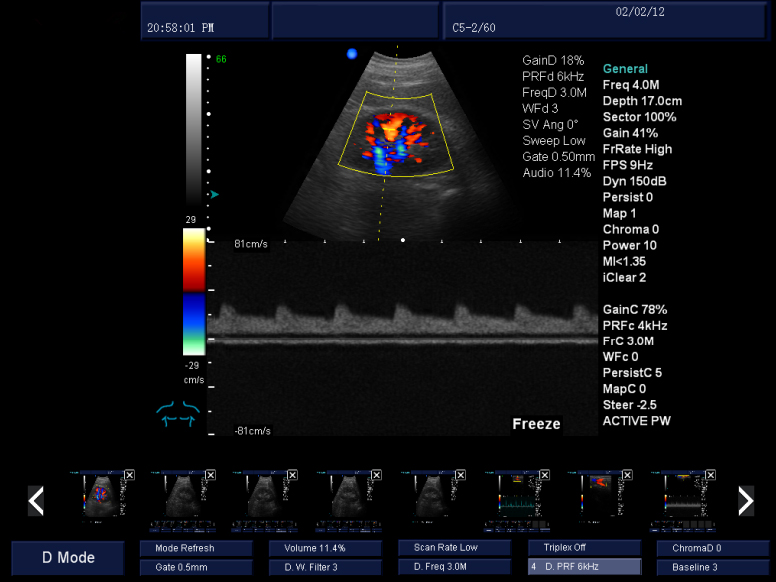

三同步顯示:二維、彩色和頻普三種模式同時(shí)處于實(shí)時(shí)狀態(tài),方便醫(yī)生對(duì)比觀察和定位取樣。 諧波成像:組織諧波成像使圖像更光滑、柔和、清晰,提升臨床診斷組織鑒別。